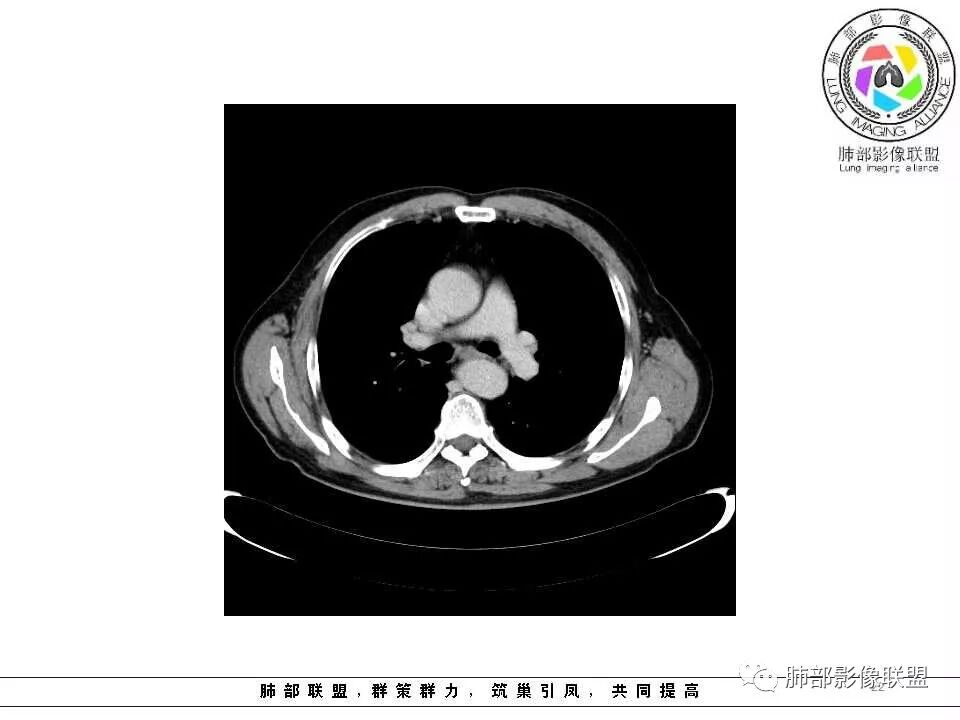

左肺上叶光滑结节影 似乎与支气管没有关系  ,给的纵隔窗病灶中心似乎点状钙化  病灶旁有更小结节,与上一年片比较 结节增大明显  考虑恶性 类癌可能

肺气肿背景,2016年左肺上叶上舌段见微结节,2017年5月左肺结节增大,密度均匀,边缘光滑锐利,与邻近血管关系密切,血管贴壁走行,外侧见尖状突起,下舌段片状影,沿着支气管走行,内有粘液栓,考虑鳞癌,鉴别小细胞肺癌。

支气管来源恶性病变,继发远端阻塞性炎症,鳞癌,类癌

彭君:

左肺上叶舌段支气管管壁略增厚 间隔一年 管壁增厚明显 向腔外突出形成结节 管腔闭塞 远端片状及斑片影 纵隔淋巴结增大 肺气肿背景 考虑鳞癌伴阻塞性炎症可能

前次片2016年4月20相应位置就有小点状病灶,2017-5-15呈结节影改变,边界膨隆,远端阻塞炎性改变,考虑肺癌,鉴别炎性结节!

老年男性,咯血1月,肺气肿背景,左肺上叶舌段见沿支气管走行分布结节,呈葫芦样改变,左肺门淋巴结肿大明显,首先考虑恶性病变,小细胞癌可能

南大标注,这几个确实结节没有阻塞支气管,感觉是在血管分叉地方。

常规腔内病灶引起远端炎症:

1、肿瘤,良性、恶性?短时间出来——恶性

2、炎性,结核、真菌多见,但是表面膨隆、光滑,不太支持,放待排

3、异物、痰栓,附近的结节不支持,最好有密度测量、强化情况

就目前的资料:我支持恶性肿瘤,待排异物